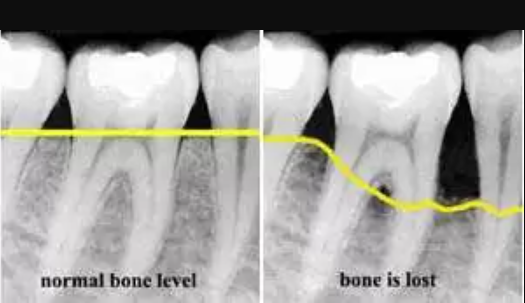

X-ray는

고에너지 전자기파를 이용해

인체의 여러 조직을 통과합니다.

각 조직의 밀도에 따라

전자기파가 소멸되는 정도가 달라지는데,

밀도가 높은 치아와 뼈는

많은 방사선을 흡수하는

반면, 연조직은 상대적으로 적게 흡수합니다.

이러한 특성 덕분에,

자연치와 뼈는 영상 상에서 밝게 나타나고,

공극이나 염증, 충치 부위는 어둡게 표현됩니다.

필름이나 디지털 센서에

도달한 방사선의 양을 바탕으로,

촬영 부위의 밝은 부분과

어두운 부분이 뚜렷하게

대비되어 영상이 생성되며,

이를 통해 전문가들은

각 조직의 밀도와 구조적 이상을

분석할 수 있습니다.